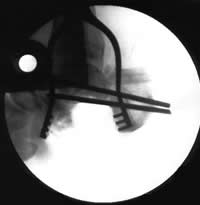

Treatment in ProgressThis intraoperative x-ray image shows the extent of infected bone that had to be removed from the foot. |